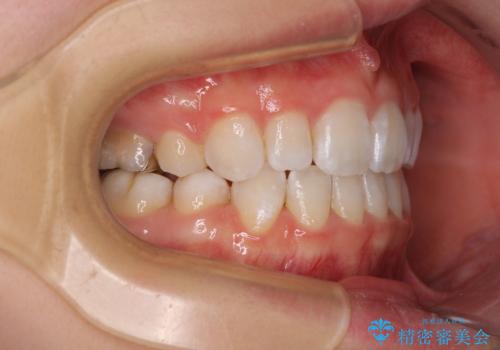

4本の歯を抜歯したことで、飛び出していた口元が引っ込み、横顔が大きく改善されました。

- 前歯の出っ歯と口元の閉じにくさを気にして来院された患者様です。

口元を積極的に引っ込めるために、上下左右の小臼歯4本を抜歯することとしました。